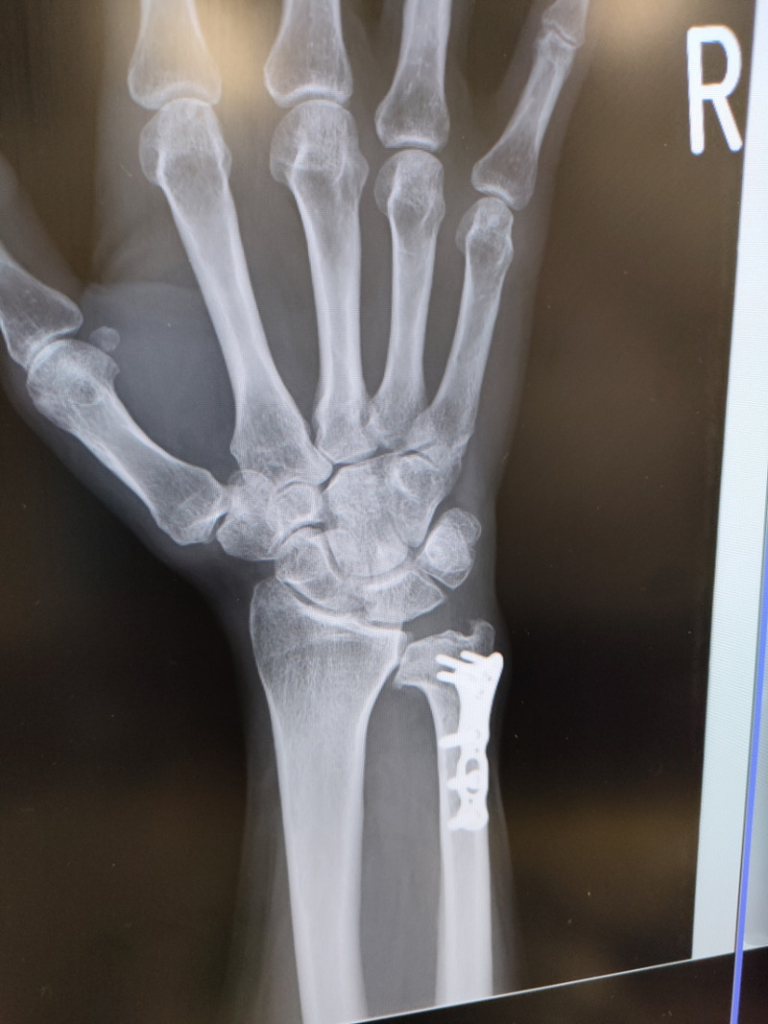

TFCC損傷尺骨突き上げ症候群druj不安定症入院手術尺骨短縮術ギプス手術跡レントゲン入院記録抜釘手術。

tfcc損傷と尺骨短縮術後㊻抜釘後その3ホンダのTFCC損傷と更年期主婦のブログ。

TFCC損傷・尺骨短縮術 入院~手術~術漁師の徒然なるブログ。

術後8ヶ月 TFCC損傷漁師の徒然なるブログ。